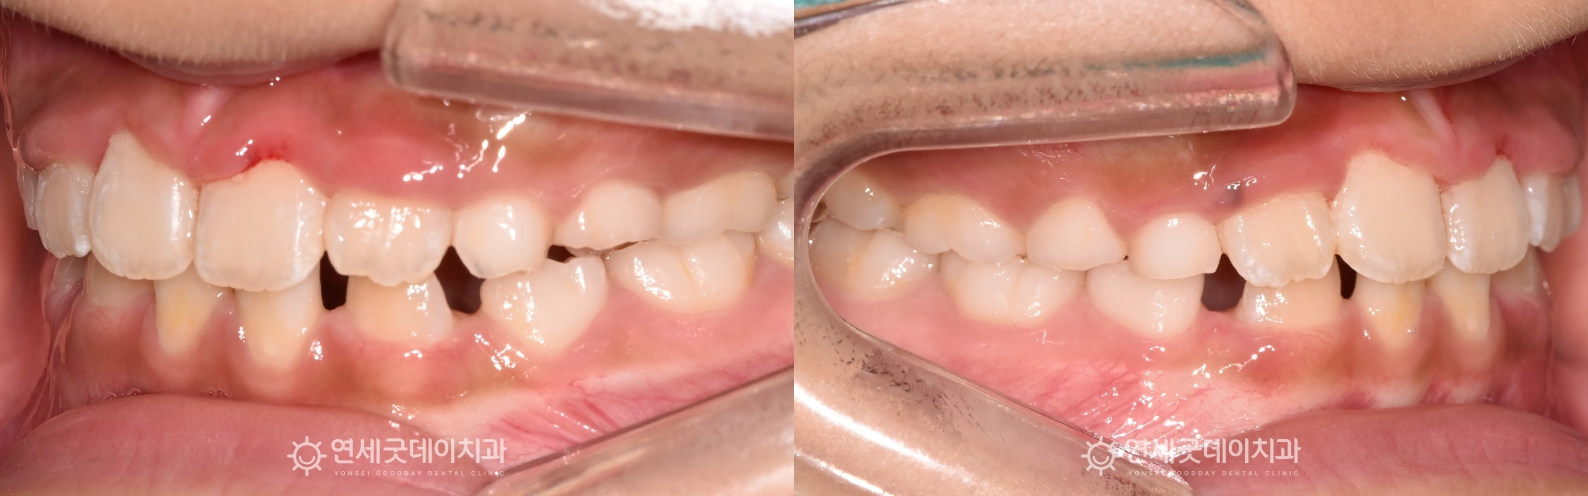

▲ 치료전 안모 (촬영시기 : 2024년 6월)

해당 어린이 환자의 경우, 프리올소와 장치 부분교정을 통해 반대교합을 개선하고

결손치 부위는 추후 2차교정 시 개선하는 치료계획을 수립했습니다.

▲ 프리올소 + 장치 부분교정 치료후 (촬영시기 : 2025년 8월)

약 1년 1개월 간의 성장기치아교정이 잘 마무리되었습니다.

8개월 동안의 프리올소 교정 후 3개월 동안 장치 부분교정을 진행했으며

윗니가 아랫니를 1~2mm 정도 덮는 정상교합으로 개선되었습니다.